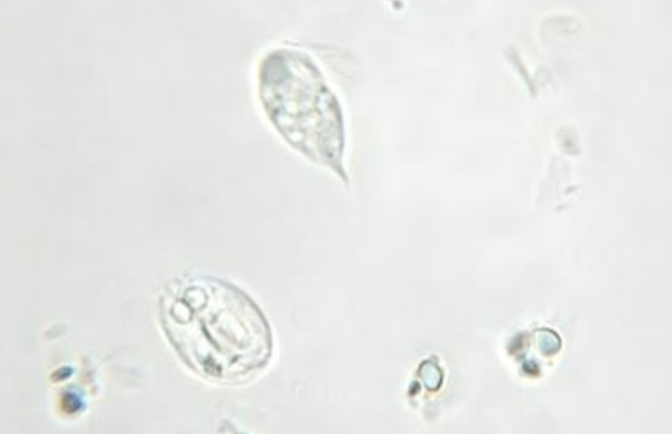

Chilomastix mesnili (cyst)

Chilomastix mesnili (cyst)

Chilomastix mesnili (troph)

Chilomastix mesnili (troph)